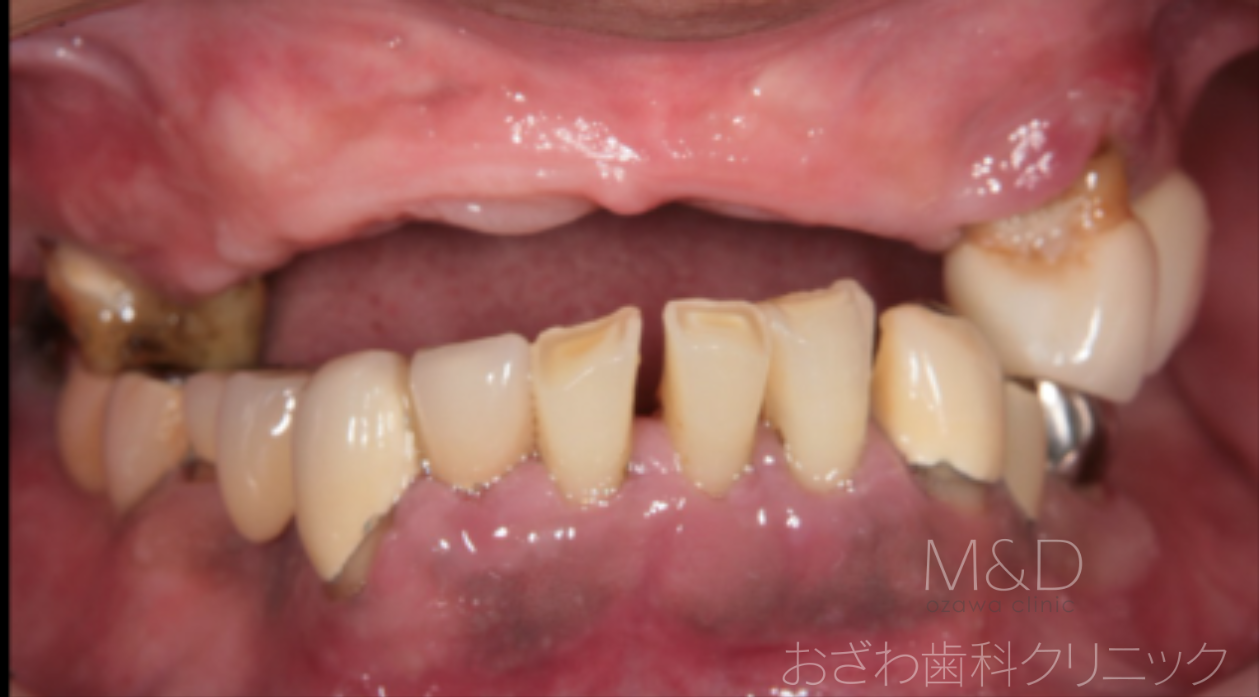

術前

主訴:上下の歯がぐらぐらして噛めない